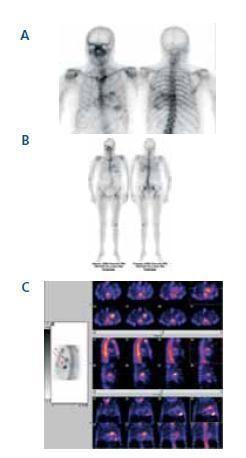

El estudio del paciente incluye, entre otras pruebas, gammagrafía ósea con 99mTc-MDP (figuras 1a, 1b y c), obteniendo imágenes de rastreo corporal completo y SPECT torácico, radiografía de tórax (figura 2) y ecocardiograma (figura 3).

La existencia de captación cardiaca y de tejidos blandos con 99mTc-MDP en pacientes con hemodiálisis ha sido descrita en algunas publicaciones2. La gammagrafía cardiaca con radiotrazadores óseos es un método no invasivo para la detección de la calcinosis cardiaca en estos pacientes3.

Figura 1a, b y c.